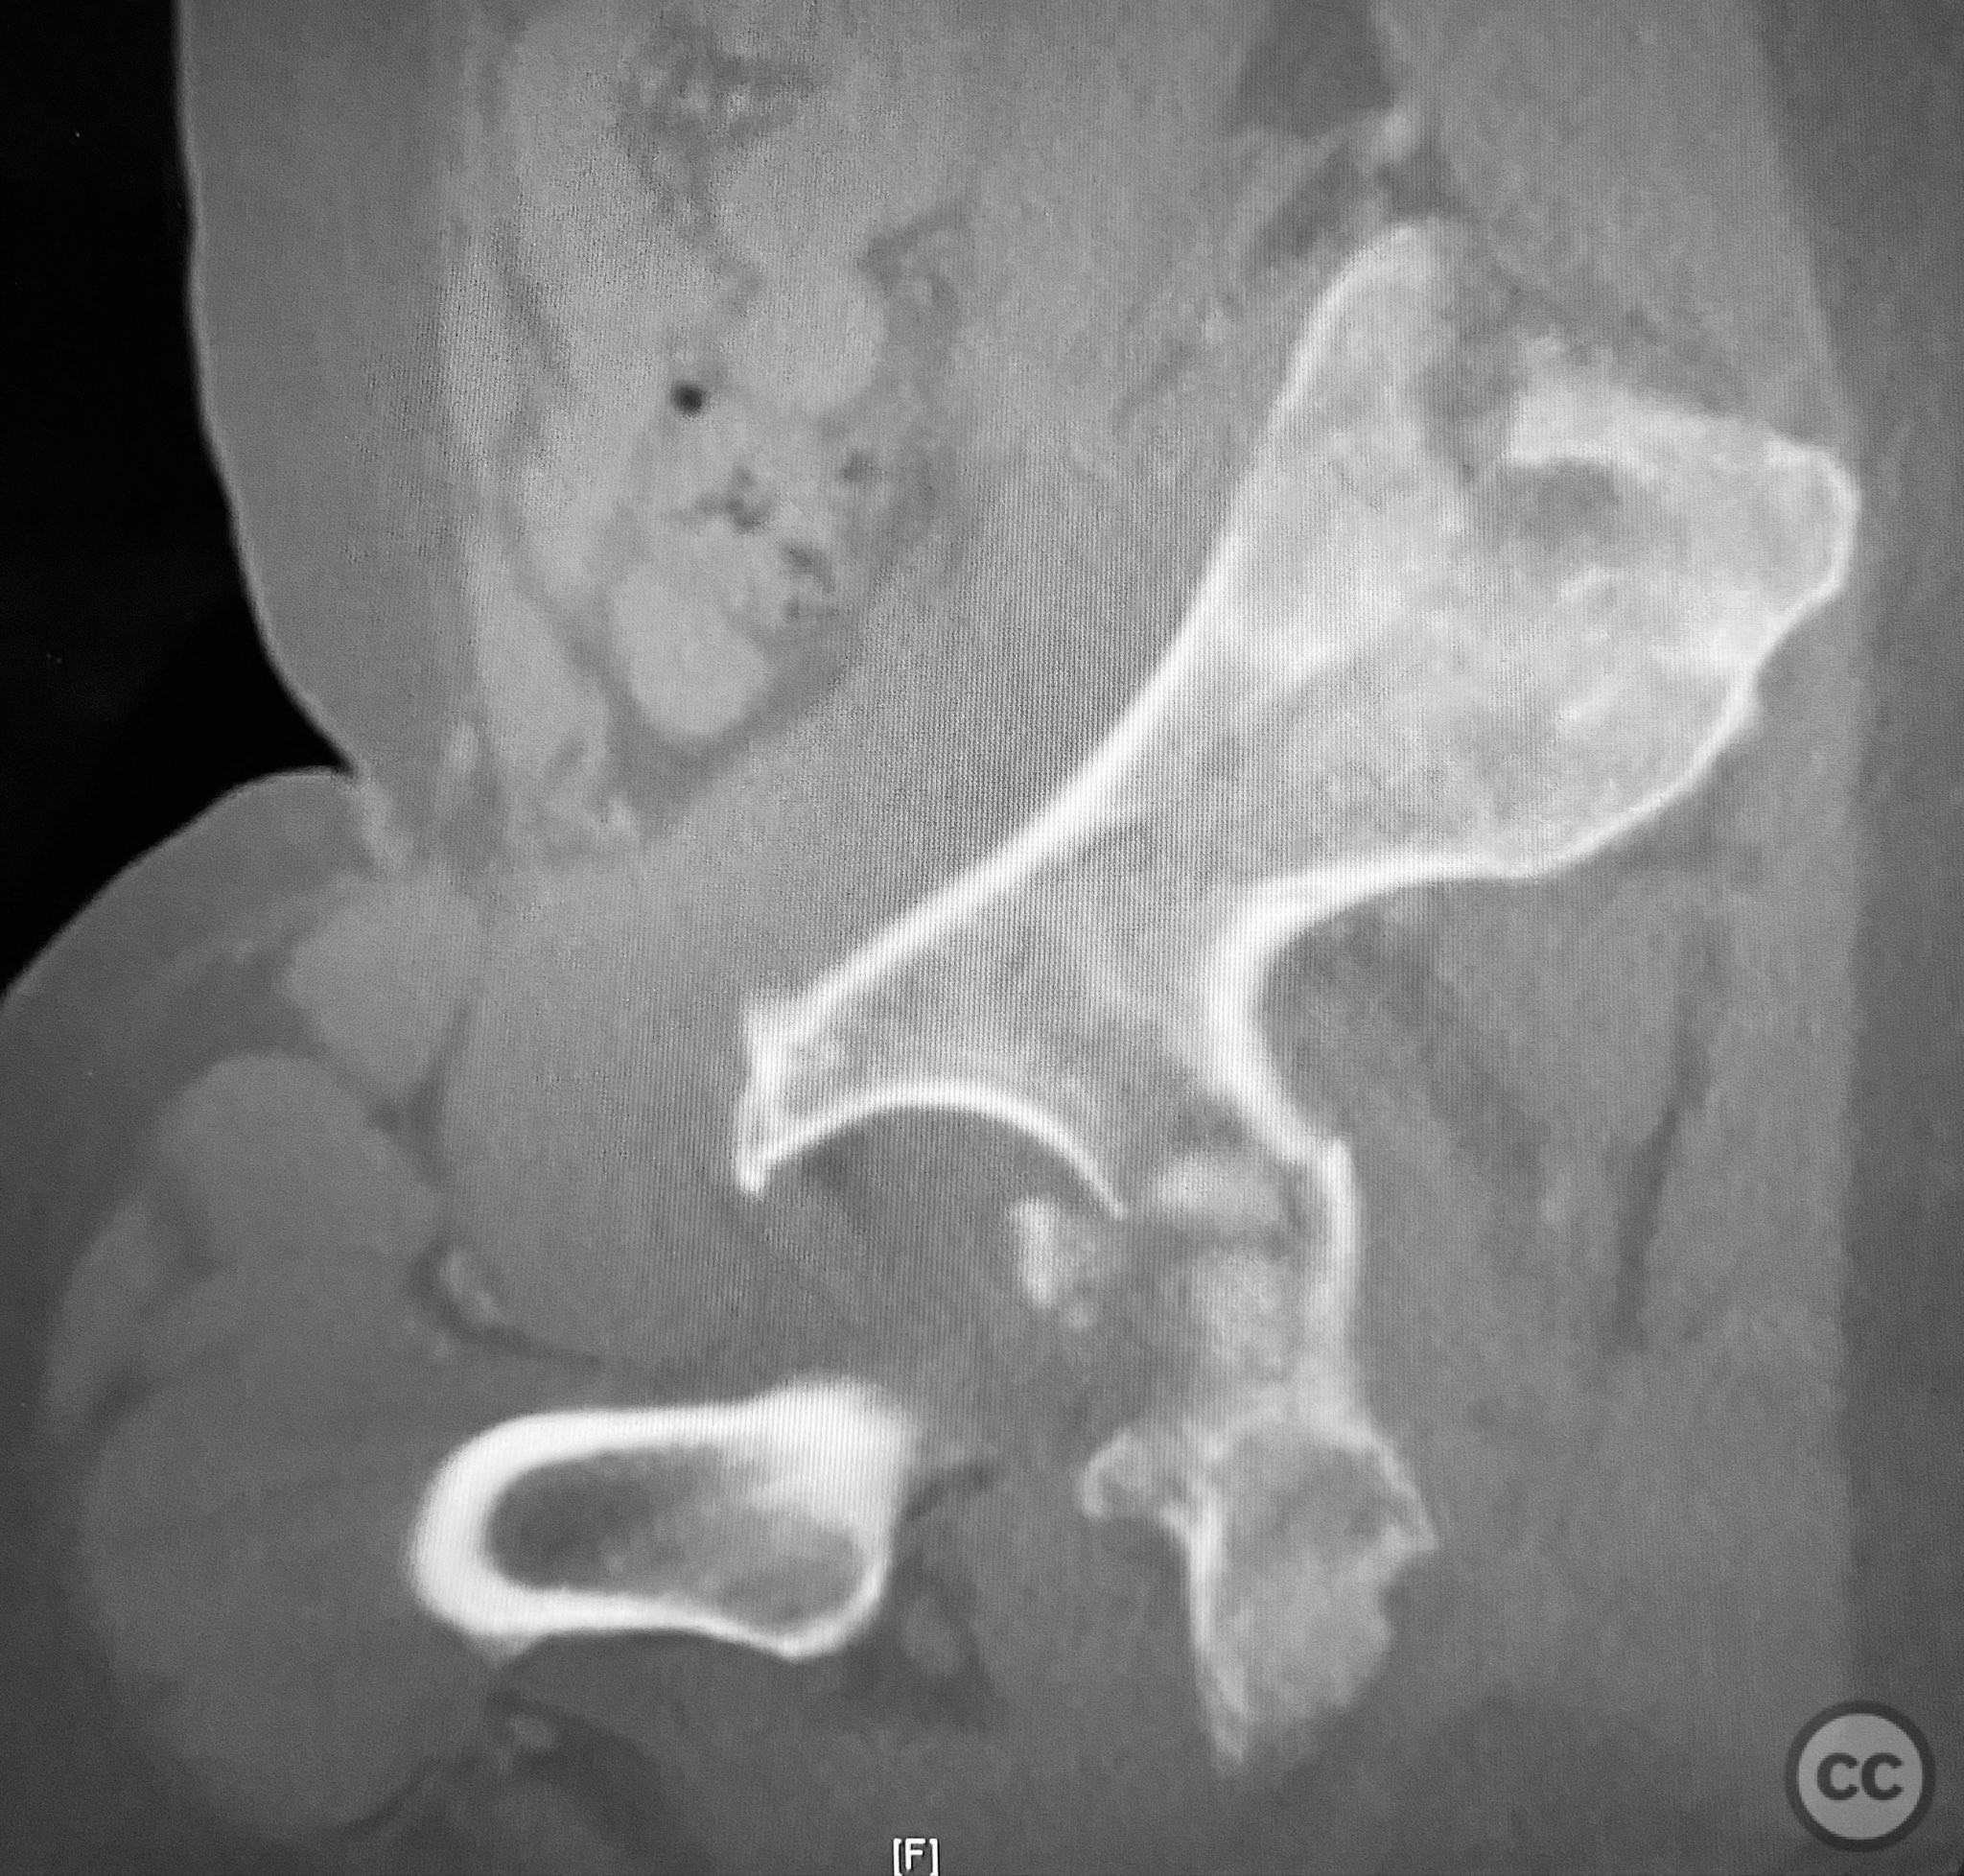

Clinical and radiological findings:  A patient sustained a posterior wall acetabular fracture-dislocation, characterized by comminution of the posterior wall, impaction of fragments into the posterior column region, and intra-articular loose fragments within the fossa acetabuli. Sagittal imaging demonstrated femoral head impalement on the intact wall, raising concern for potential irreducibility. Coronal and axial CT images revealed acetabular and femoral head impactions, peripheral wall comminution, incomplete fracture extension at the acetabular notch and quadrilateral surface, and an articular fragment within the joint. Surface renderings confirmed the extent of peripheral wall comminution and impaction. Despite these findings, a closed manipulative reduction was successfully achieved, resulting in a congruent reduction on post-reduction imaging.